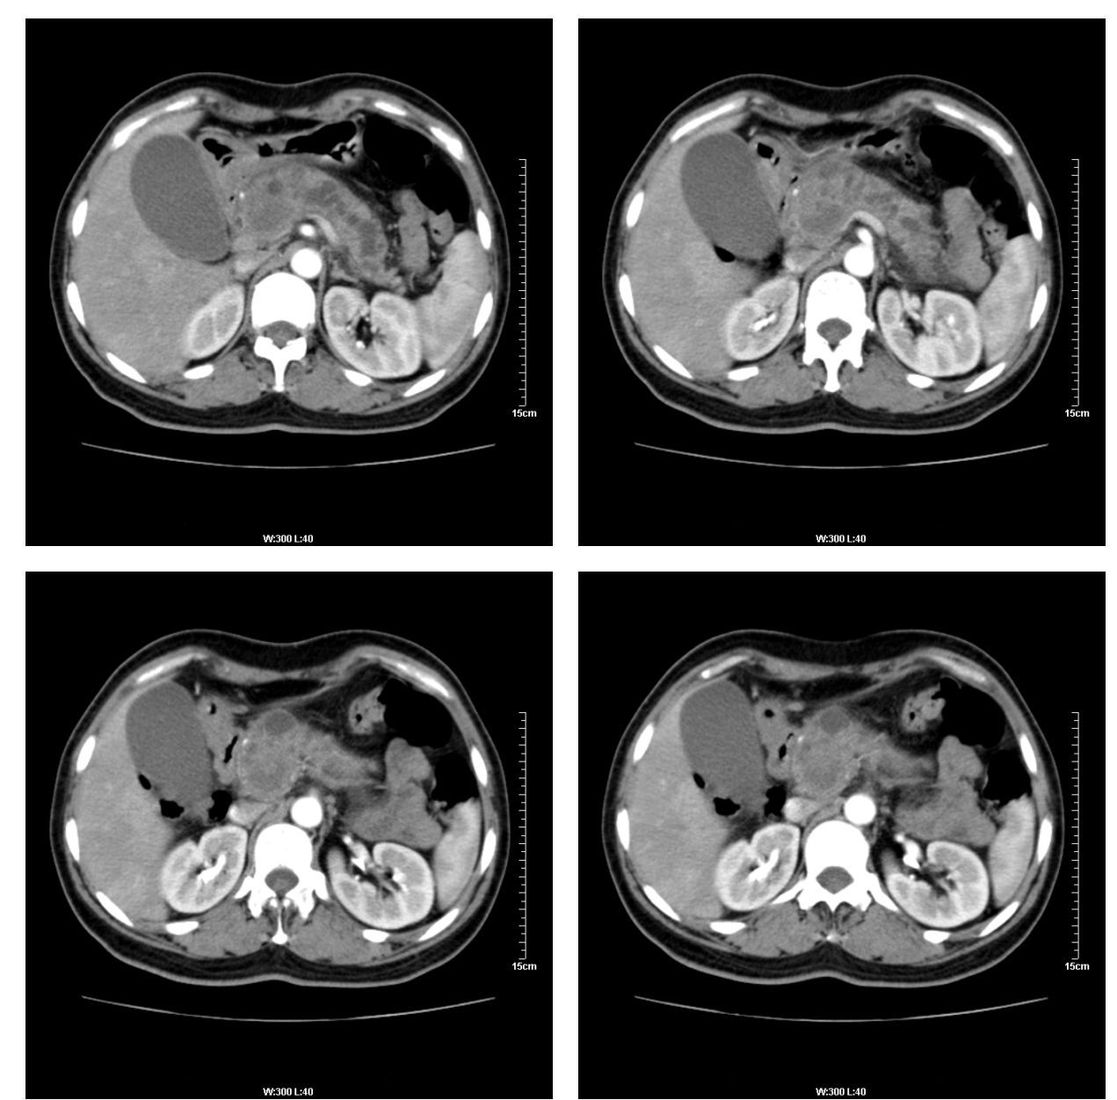

标题: CT13800:女性,52岁。腹痛、腹胀、消瘦及乏力5个月。 [打印本页]

标题: CT13800:女性,52岁。腹痛、腹胀、消瘦及乏力5个月。

胰腺癌可能大

考虑胰头癌

考虑胰腺囊腺癌。

考虑胰头癌可能。

考虑胰头癌可能性大。